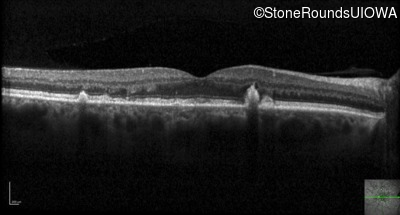

Optical Coherence Tomography - Right - 20/20 -1 sc

Exemplar / OCT Stack

OCT Stack